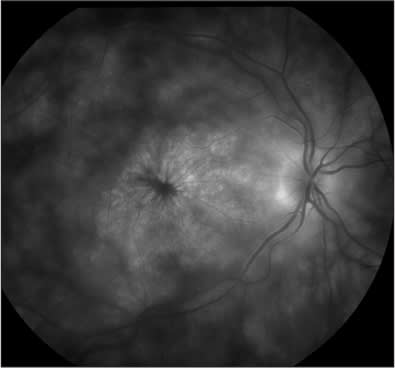

The International Uveitis Study Group9 established guidelines for the treatment of severe ocu lar inflammatory diseases. Immunomodulatory therapy is indicated as first-line treatment of Behçet disease with retinal involvement, sympathetic ophthalmia (Figure 2), rheumatoid sclerouveitis and Vogt-Koyanagi-Harada (VKH; Figure 3) syndrome (Table 2).

Figure 3. Fluorescein angiogram of Vogt-Koyangi-Harada with serous retinal detachment and multiple pinpoint hyperfluorescent dots with leakage.